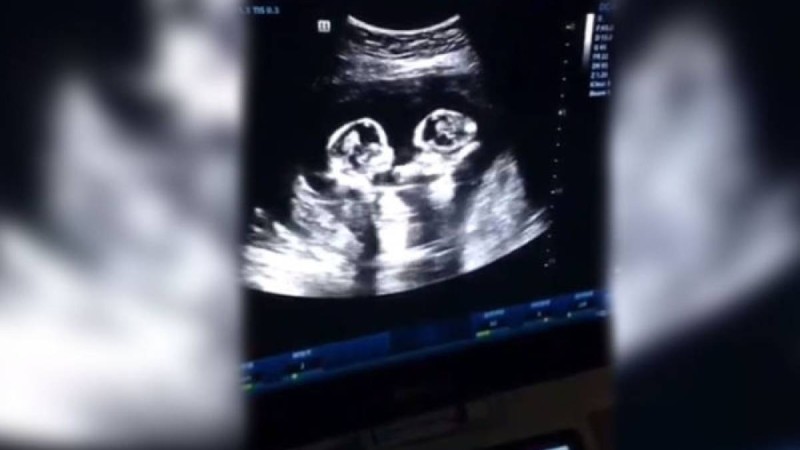

Құрсақта жатқан егіздер "төбелесті" - видео НҰР-СҰЛТАН, 21 сәуір - Sputnik. Қытайда ультра дыбыстық зерттеу кезінде ата-ана жүк... 21 сәуір 2019 • Шоу-бизнес